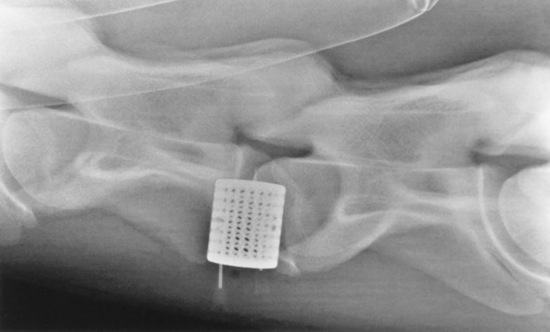

Surgical intervention is the most widely reported treatment for CVSM and is indicated to stop repetitive trauma to the spinal cord.1894-1897 The goals of surgical intervention are to stabilize the cervical vertebrae and decompress the spinal cord. Cervical vertebral interbody fusion (ventral stabilization) provides intervertebral stability for horses with dynamic spinal cord compression. The affected cervical vertebrae are fused in the extended position to provide immediate relief of compression and prevent repetitive spinal cord trauma (Fig. 35-31).

Fig. 35-31 Intraoperative radiograph of third and fourth cervical vertebrae during cervical vertebral interbody fusion. The stainless steel basket is placed in the ventral aspect of the vertebral bodies, spanning the intervertebral disk and vertebral endplates, at the C3-C4 articulation.